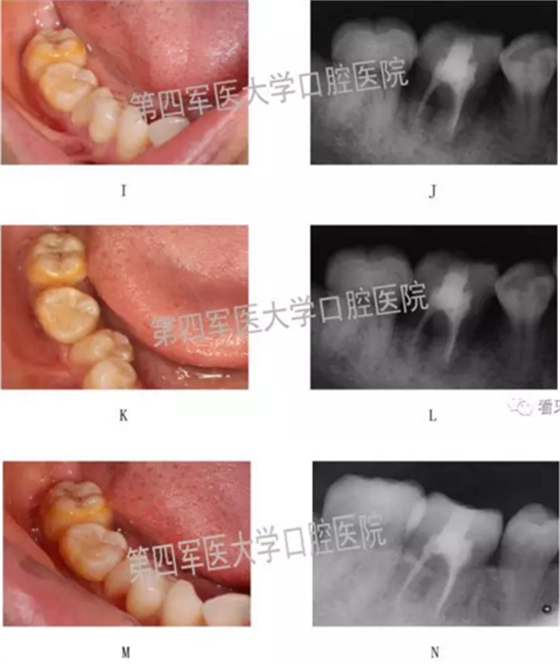

四、典型病例:

第四軍醫(yī)大學(xué)口腔醫(yī)院